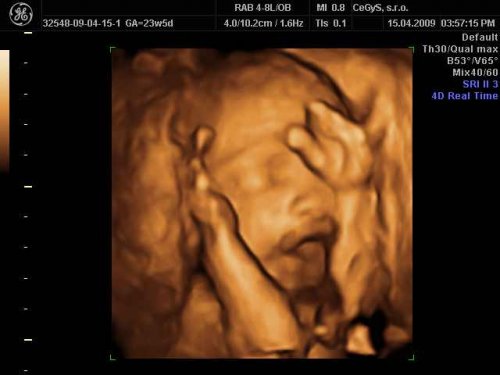

Čakáme bábo